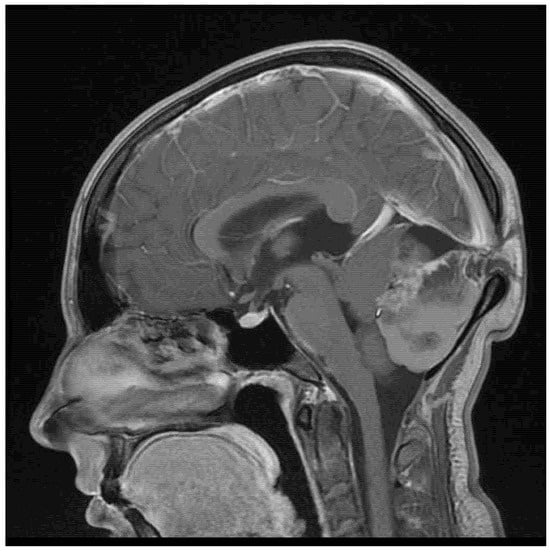

Mature Teratoma of the Cerebellum with Formed Extracranial Component

| 22/female | cerebellum—midline | mature teratoma | severe headache | current case |